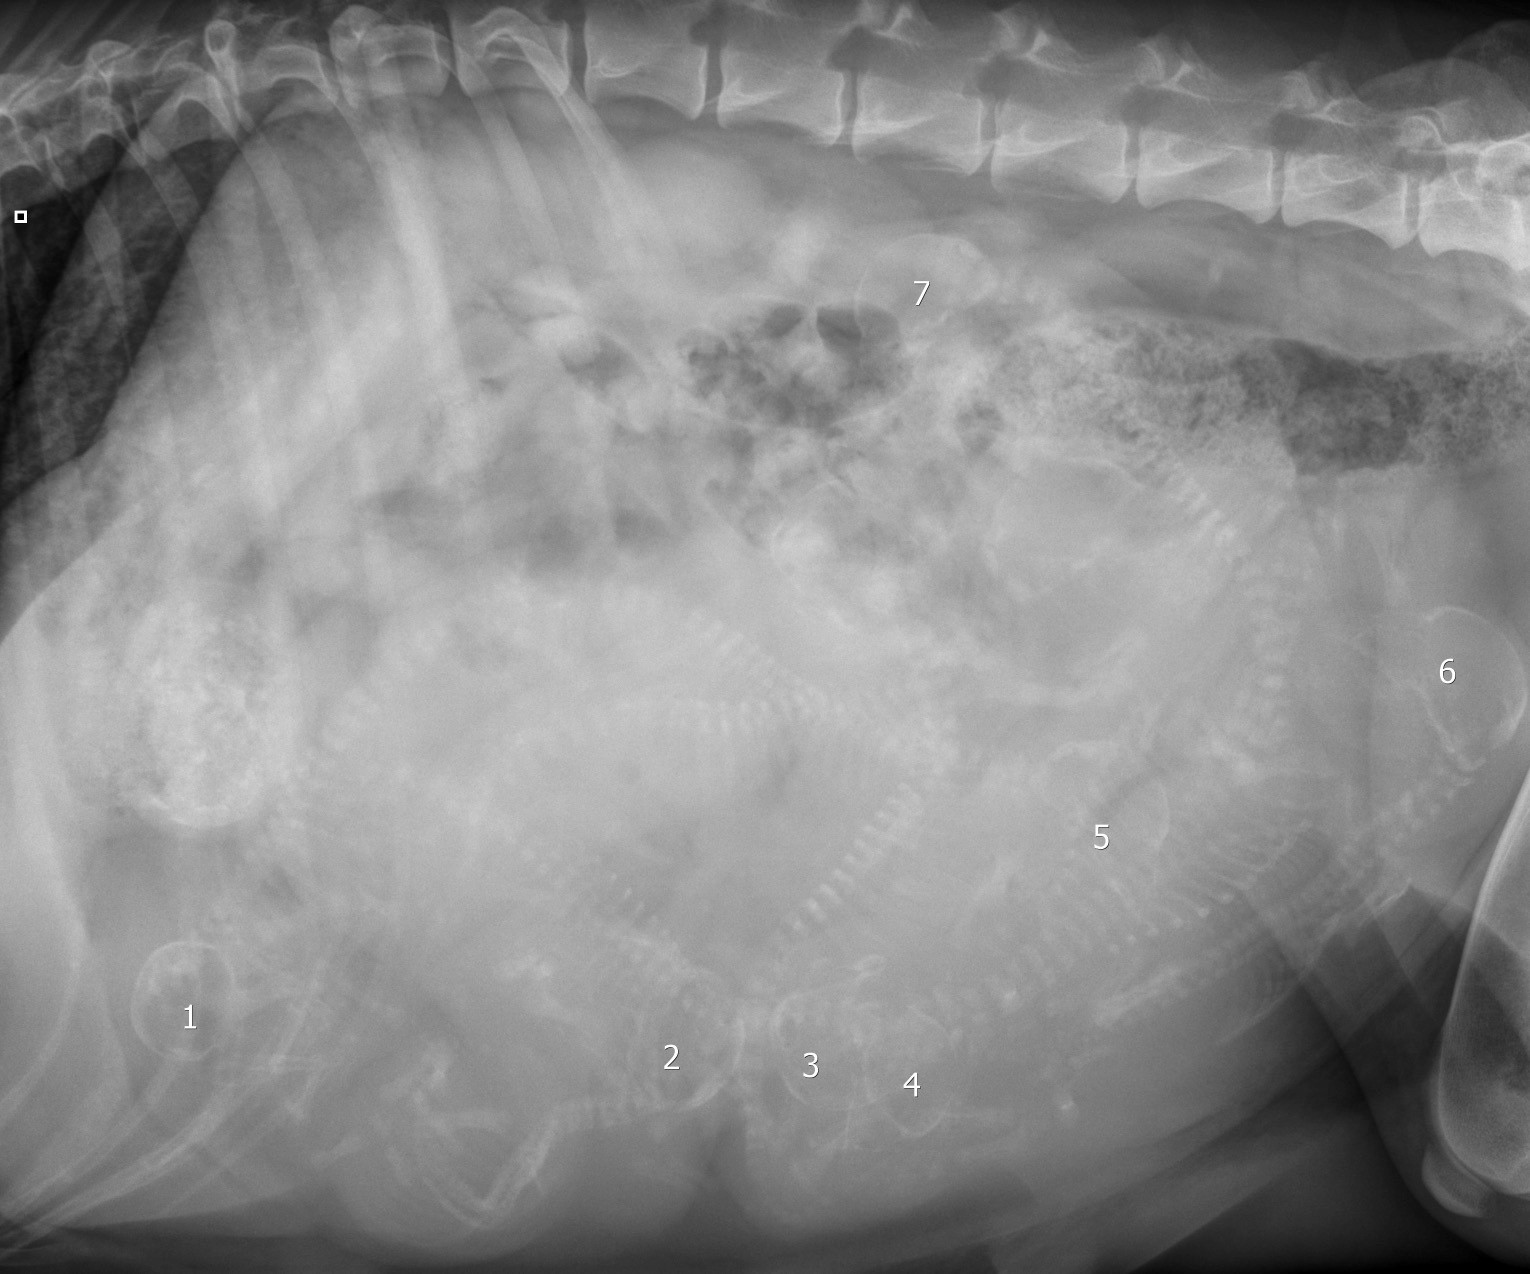

Lasketaanko yhdessä? Sia Sophia kävi tiineys RTGSSÄ....

Katokaa, siinä he nyt ovat, meidän tuleva O pentueemme! Kylläpä he ovat sieviä ja komeita 😛

Ja tämän verran saimme lääkärissä laskettua... Tuntuu kylläkin että kuvassa on 1 mysteeripentu joten lopullinen lukema olisi?

Olisiko niitä sittenkin 8?